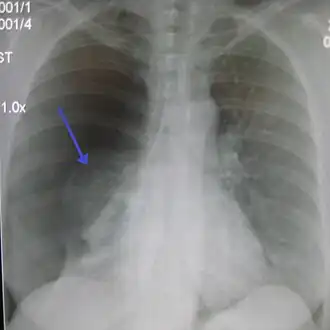

Pneumotorax

Diagnosticul se bazează pe apariția brutală a dispneei, durerea toracică violentă și atroce, fenomenele grave de asfixie, abolirea vibrațiilor vocale, hipersonoritate și tăcere la auscultație. În cele mai multe cazuri, pentru diagnostic se folosește radiografia toracică. Medicul specialist poate recomanda, de asemenea, analize sangvine care măsoară nivelul oxigenului din sânge. Tomografia computerizata (CT) sau ecografia pot fi necesare la diagnosticul severității bolii și la alcătuirea schemei de tratament.